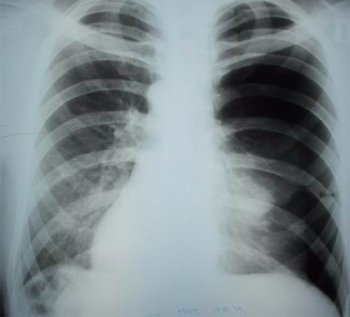

Главным методом диагностики пневмоторакса является рентгенография грудной клетки. Исследование проводится в двух позициях: стоя и лежа.

Характерные признаки:

- Наличие тонкой тени от висцеральной плевры, отделенной от грудной клетки.

- Смещение органов средостения (сердца, трахеи, сосудов) в сторону, противоположную поражению.

- Образование небольшого плеврального выпота на стороне патологического процесса.

- Рентгенологическим признаком пневмоторакса в горизонтальном положении является появление глубокой борозды, вызванной увеличением угла между ребрами и диафрагмой.

Важно помнить, что исследование следует проводить при нормальной глубине вдоха. Принудительное дыхание может ухудшить состояние пациента и повысить риск асфиксии.